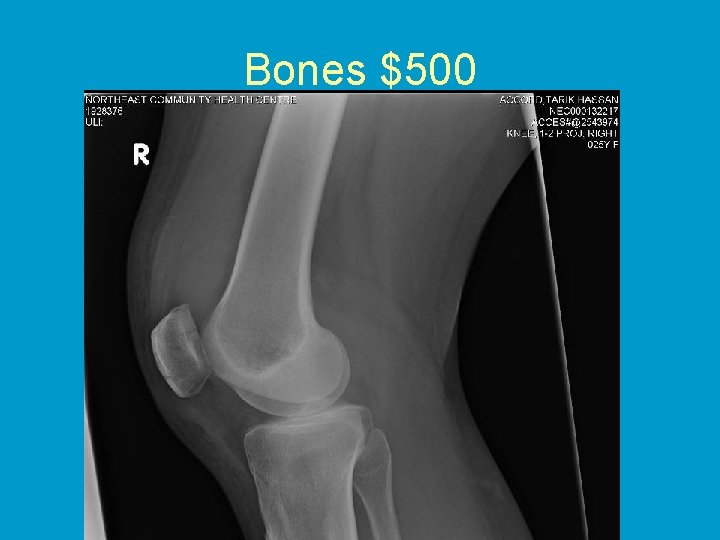

Bones $500 • A 25 year old female fell onto her knee:

Bones $500

Bones $500 • Patellar fracture • Treatment?

Patellar Fracture • Non-surgical – – Undisplaced Vertical Peripheral No step-off • Surgical – Displaced – Horizontal